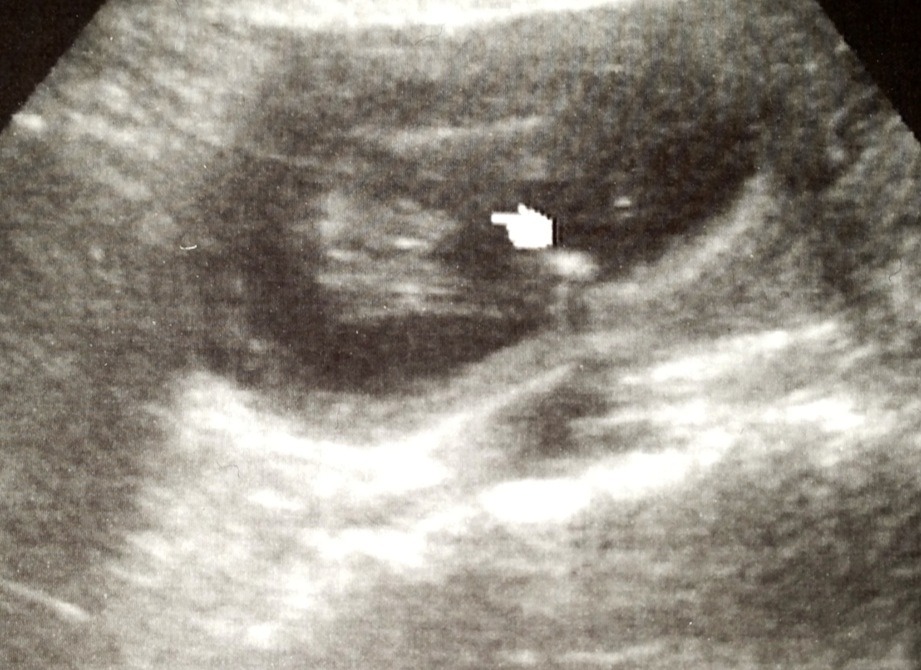

Ok, had a quick scan at 15w0d to peek at gender. She first said girl for a while, then changed her mind half way through the scan. I see its obviously protruding, but the 3 lines are making me crazy! What do you think? :suprise:

Attachment 8634Attachment 8635Attachment 8636